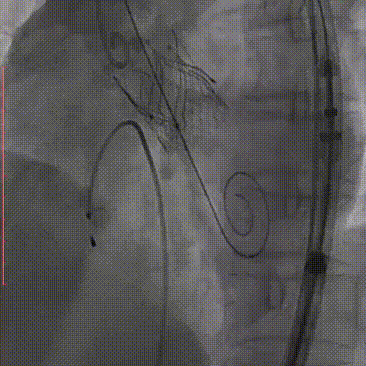

2026年伊始,TaurusTrio经导管主动脉瓣系统在复旦大学附属中山医院,浙江大学医学院附属第二医院,中国医学科学院阜外医院,首都医科大学附属北京安贞医院,四川大学华西医院等多家临床中心成功开展上市后全国首批植入。这不仅是TaurusTrio正式走向广泛临床应用的重要里程碑,更标志着中国单纯主动脉瓣反流介入治疗正式迈入了“心键合璧”的全新纪元。